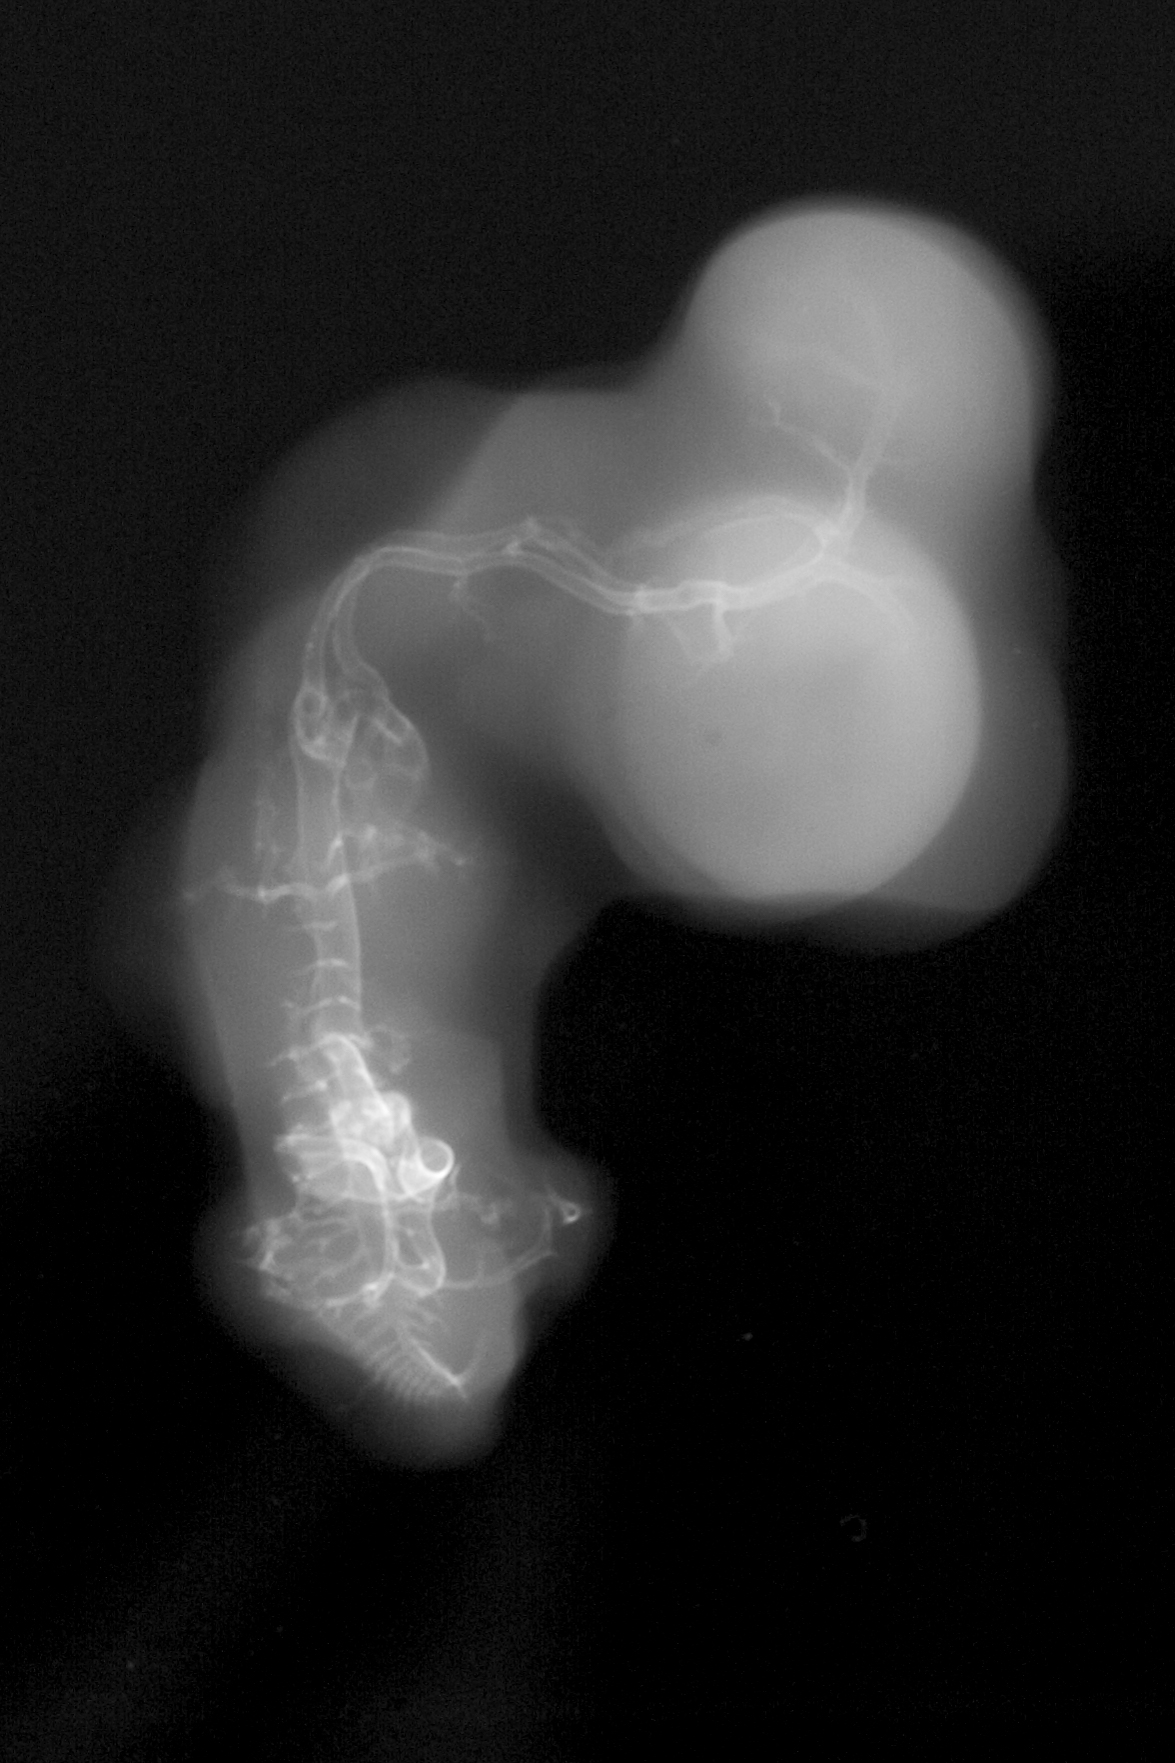

Chick Embryo Microangiography

Hamburger-Hamilton (HH) Stage 28 (approx. 5.5 - 6 days)

X-Ray Micrographs